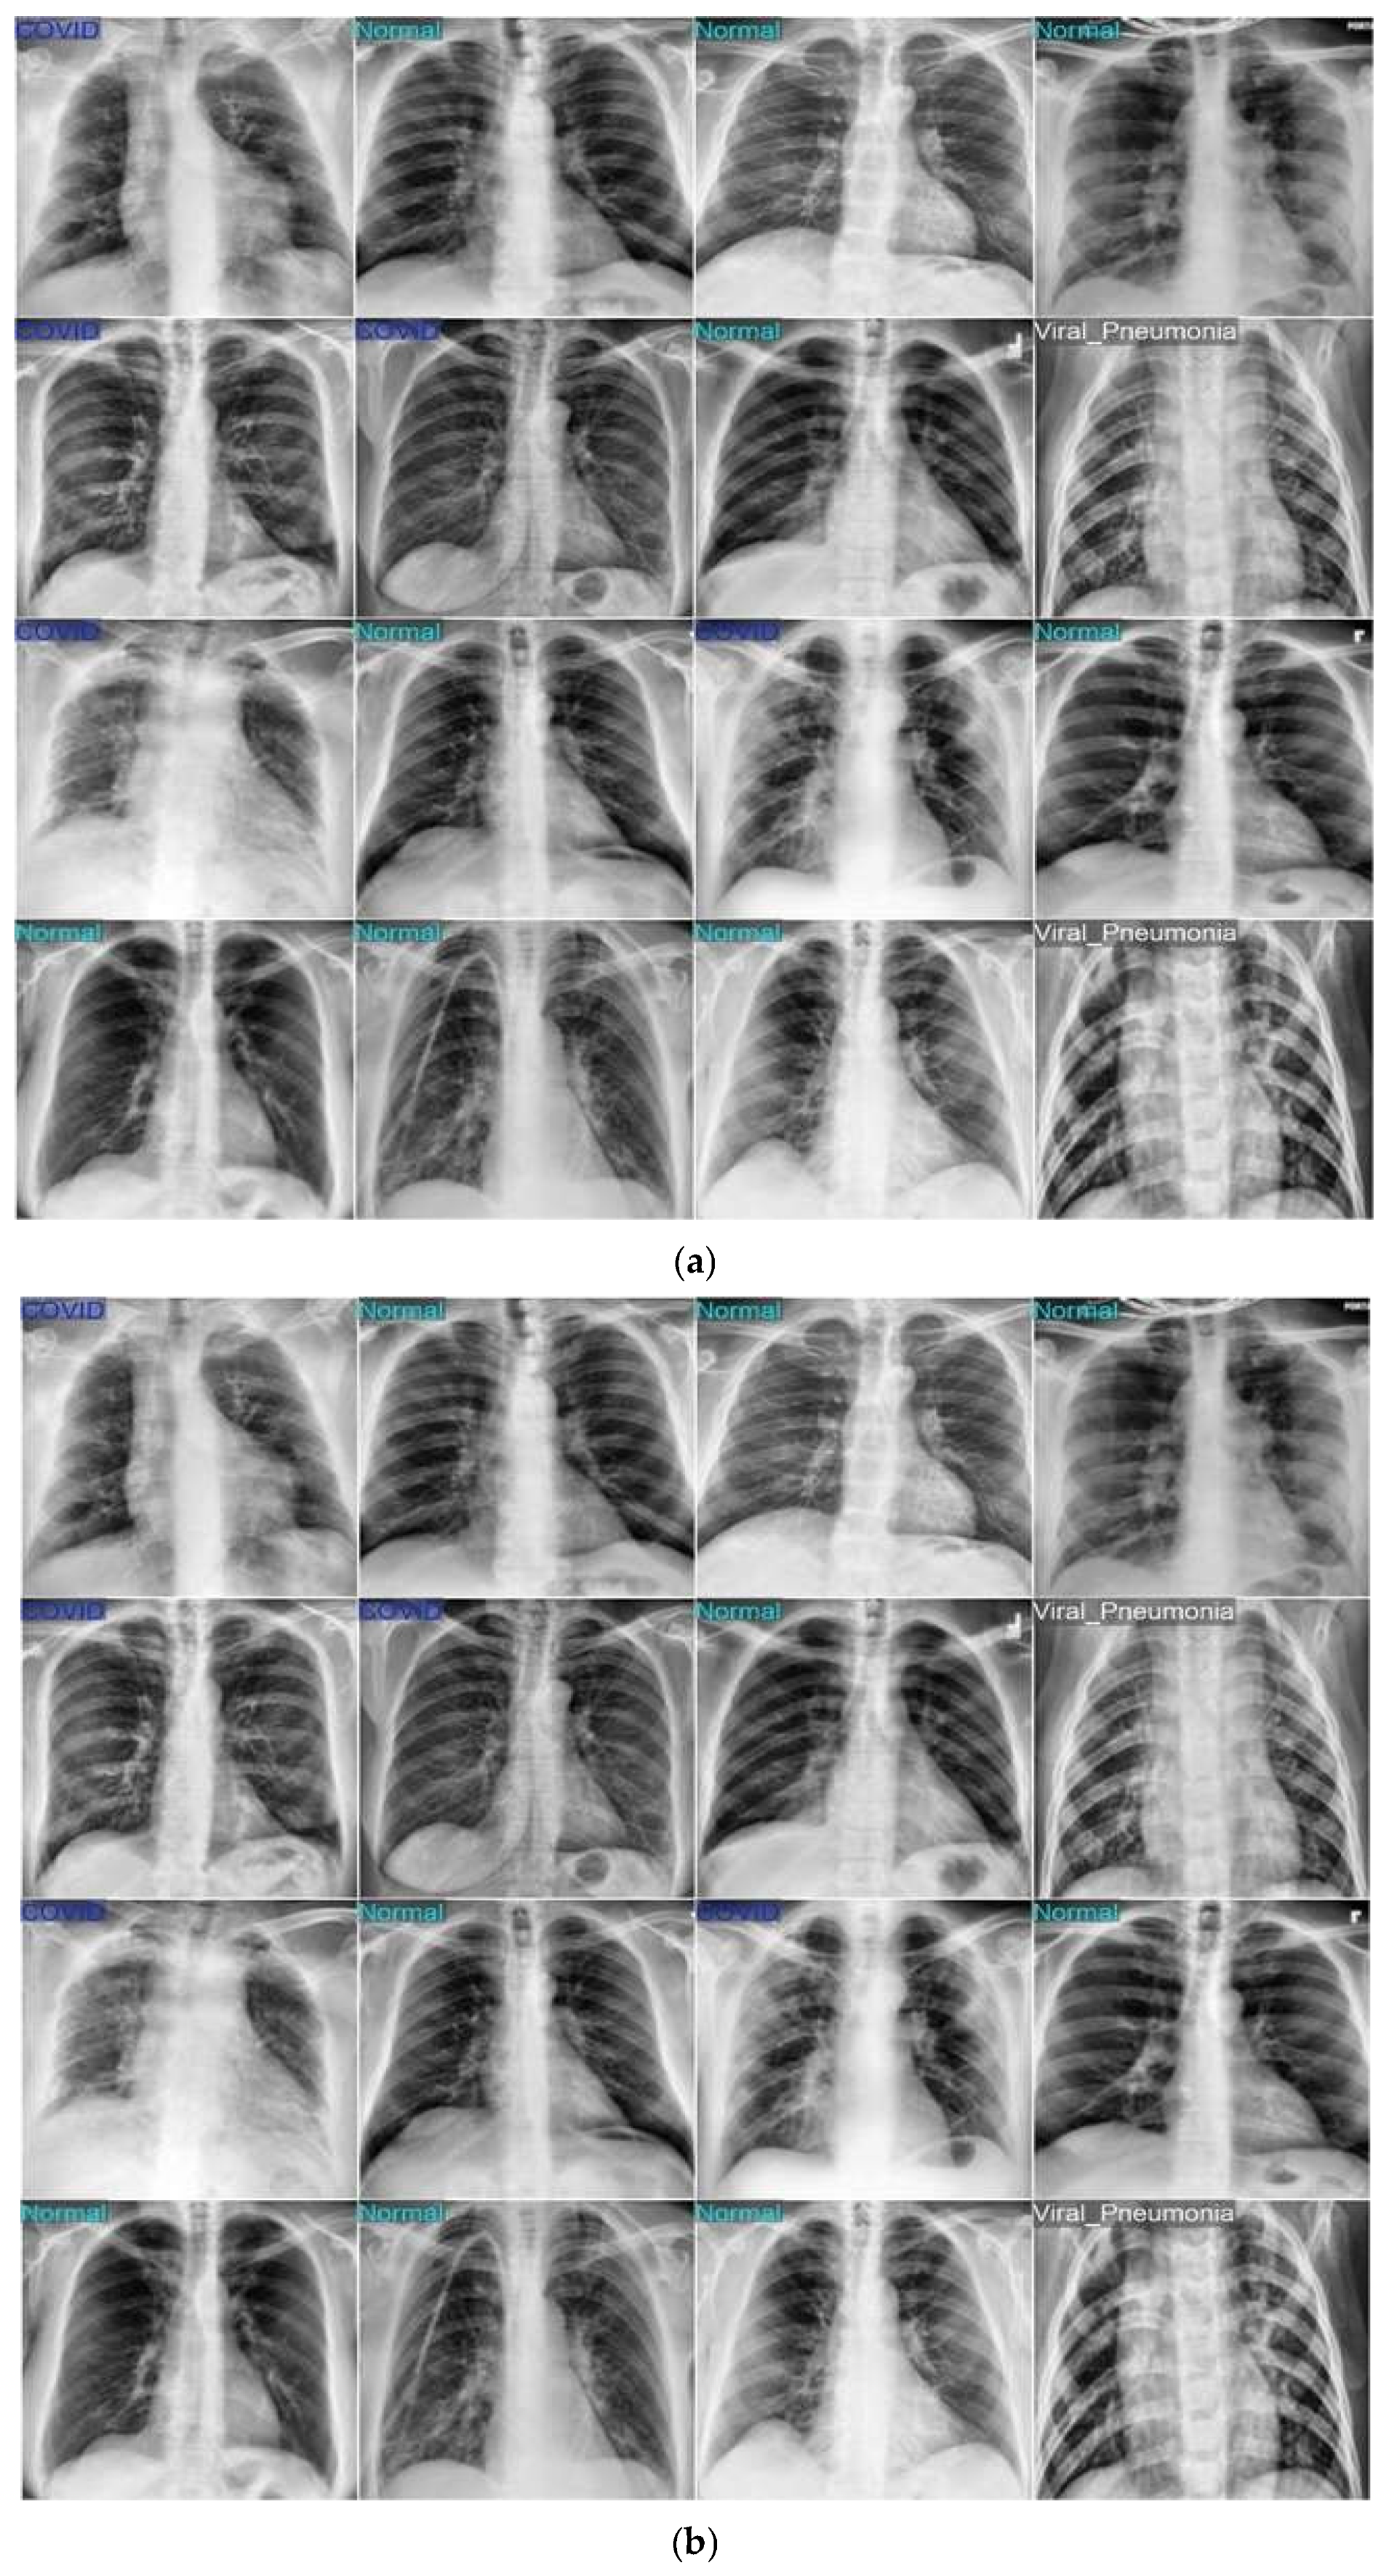

The first dataset is the COVID-19 Radiography Database, compiled and made publicly available by Tawsifur Rahman et al. on Kaggle [45]. This dataset comprises over 21,000 posterior–anterior (PA) view chest X-ray images divided into four categories: COVID-19 (3616 images), Normal (10,192 images), Lung Opacity (6012 images), and Viral Pneumonia (1345 images). The images are stored in JPEG format and annotated by clinical professionals. This dataset is widely recognized in the research community for its high-quality annotations and balanced representation of respiratory classes, making it suitable for both binary and multiclass classification tasks.

3.1.2. Dataset 2: Chest X-Ray (COVID-19 & Pneumonia)

The second dataset is the Chest X-ray (COVID-19 & Pneumonia) dataset, curated by Prashant Mohan and available on Kaggle [46]. It contains a total of 6432 chest X-ray images, categorized into three diagnostic classes: COVID-19 (1252 images), Pneumonia (3427 images), and Normal (1753 images). All images are in JPEG format and primarily captured in PA orientation. This dataset is particularly useful due to its balanced structure and clinical relevance in detecting COVID-19 and pneumonia symptoms from radiographic features. Its compact size and well-separated class structure make it ideal for rapid model prototyping and benchmarking.

When trained and tested on the COVID-19 Radiography Database, the proposed YOLOv11-based pneumonia detection model achieved outstanding performance across all three classes—COVID-19, Normal, and Pneumonia. Figure 4 illustrates the model’s learning behavior, with both training and validation loss steadily decreasing over successive epochs and training accuracy consistently improving, indicating effective convergence without signs of overfitting. The confusion matrix in Figure 5 confirms the high classification accuracy, with only a few misclassifications and strong sensitivity and specificity for each category. Visual examples in Figure 6 further validates these results, showing a close match between ground-truth labels (panel a) and the model’s predictions (panel b). The high level of agreement across diverse chest X-ray samples highlights the framework’s reliability and robustness in accurately distinguishing between COVID-19, normal, and pneumonia cases.

Using the second dataset (Chest X-ray COVID-19 & Pneumonia), the proposed YOLOv11 framework achieved consistently strong outcomes across all three classes. Figure 8a–c show the training behavior, where both training and validation losses steadily declined, and accuracy quickly rose above 98% before stabilizing—indicating effective convergence without evidence of overfitting. The confusion matrix in Figure 9 highlights only a small number of misclassifications: 20 Normal scans predicted as Pneumonia, 5 Pneumonia cases classified as Normal, and a single Pneumonia image mislabeled as COVID-19. This demonstrates clear class separation, particularly for COVID-19, which reached near-perfect accuracy. Figure 10 further illustrates this reliability, as predicted labels closely matched ground-truth annotations with minimal discrepancies.